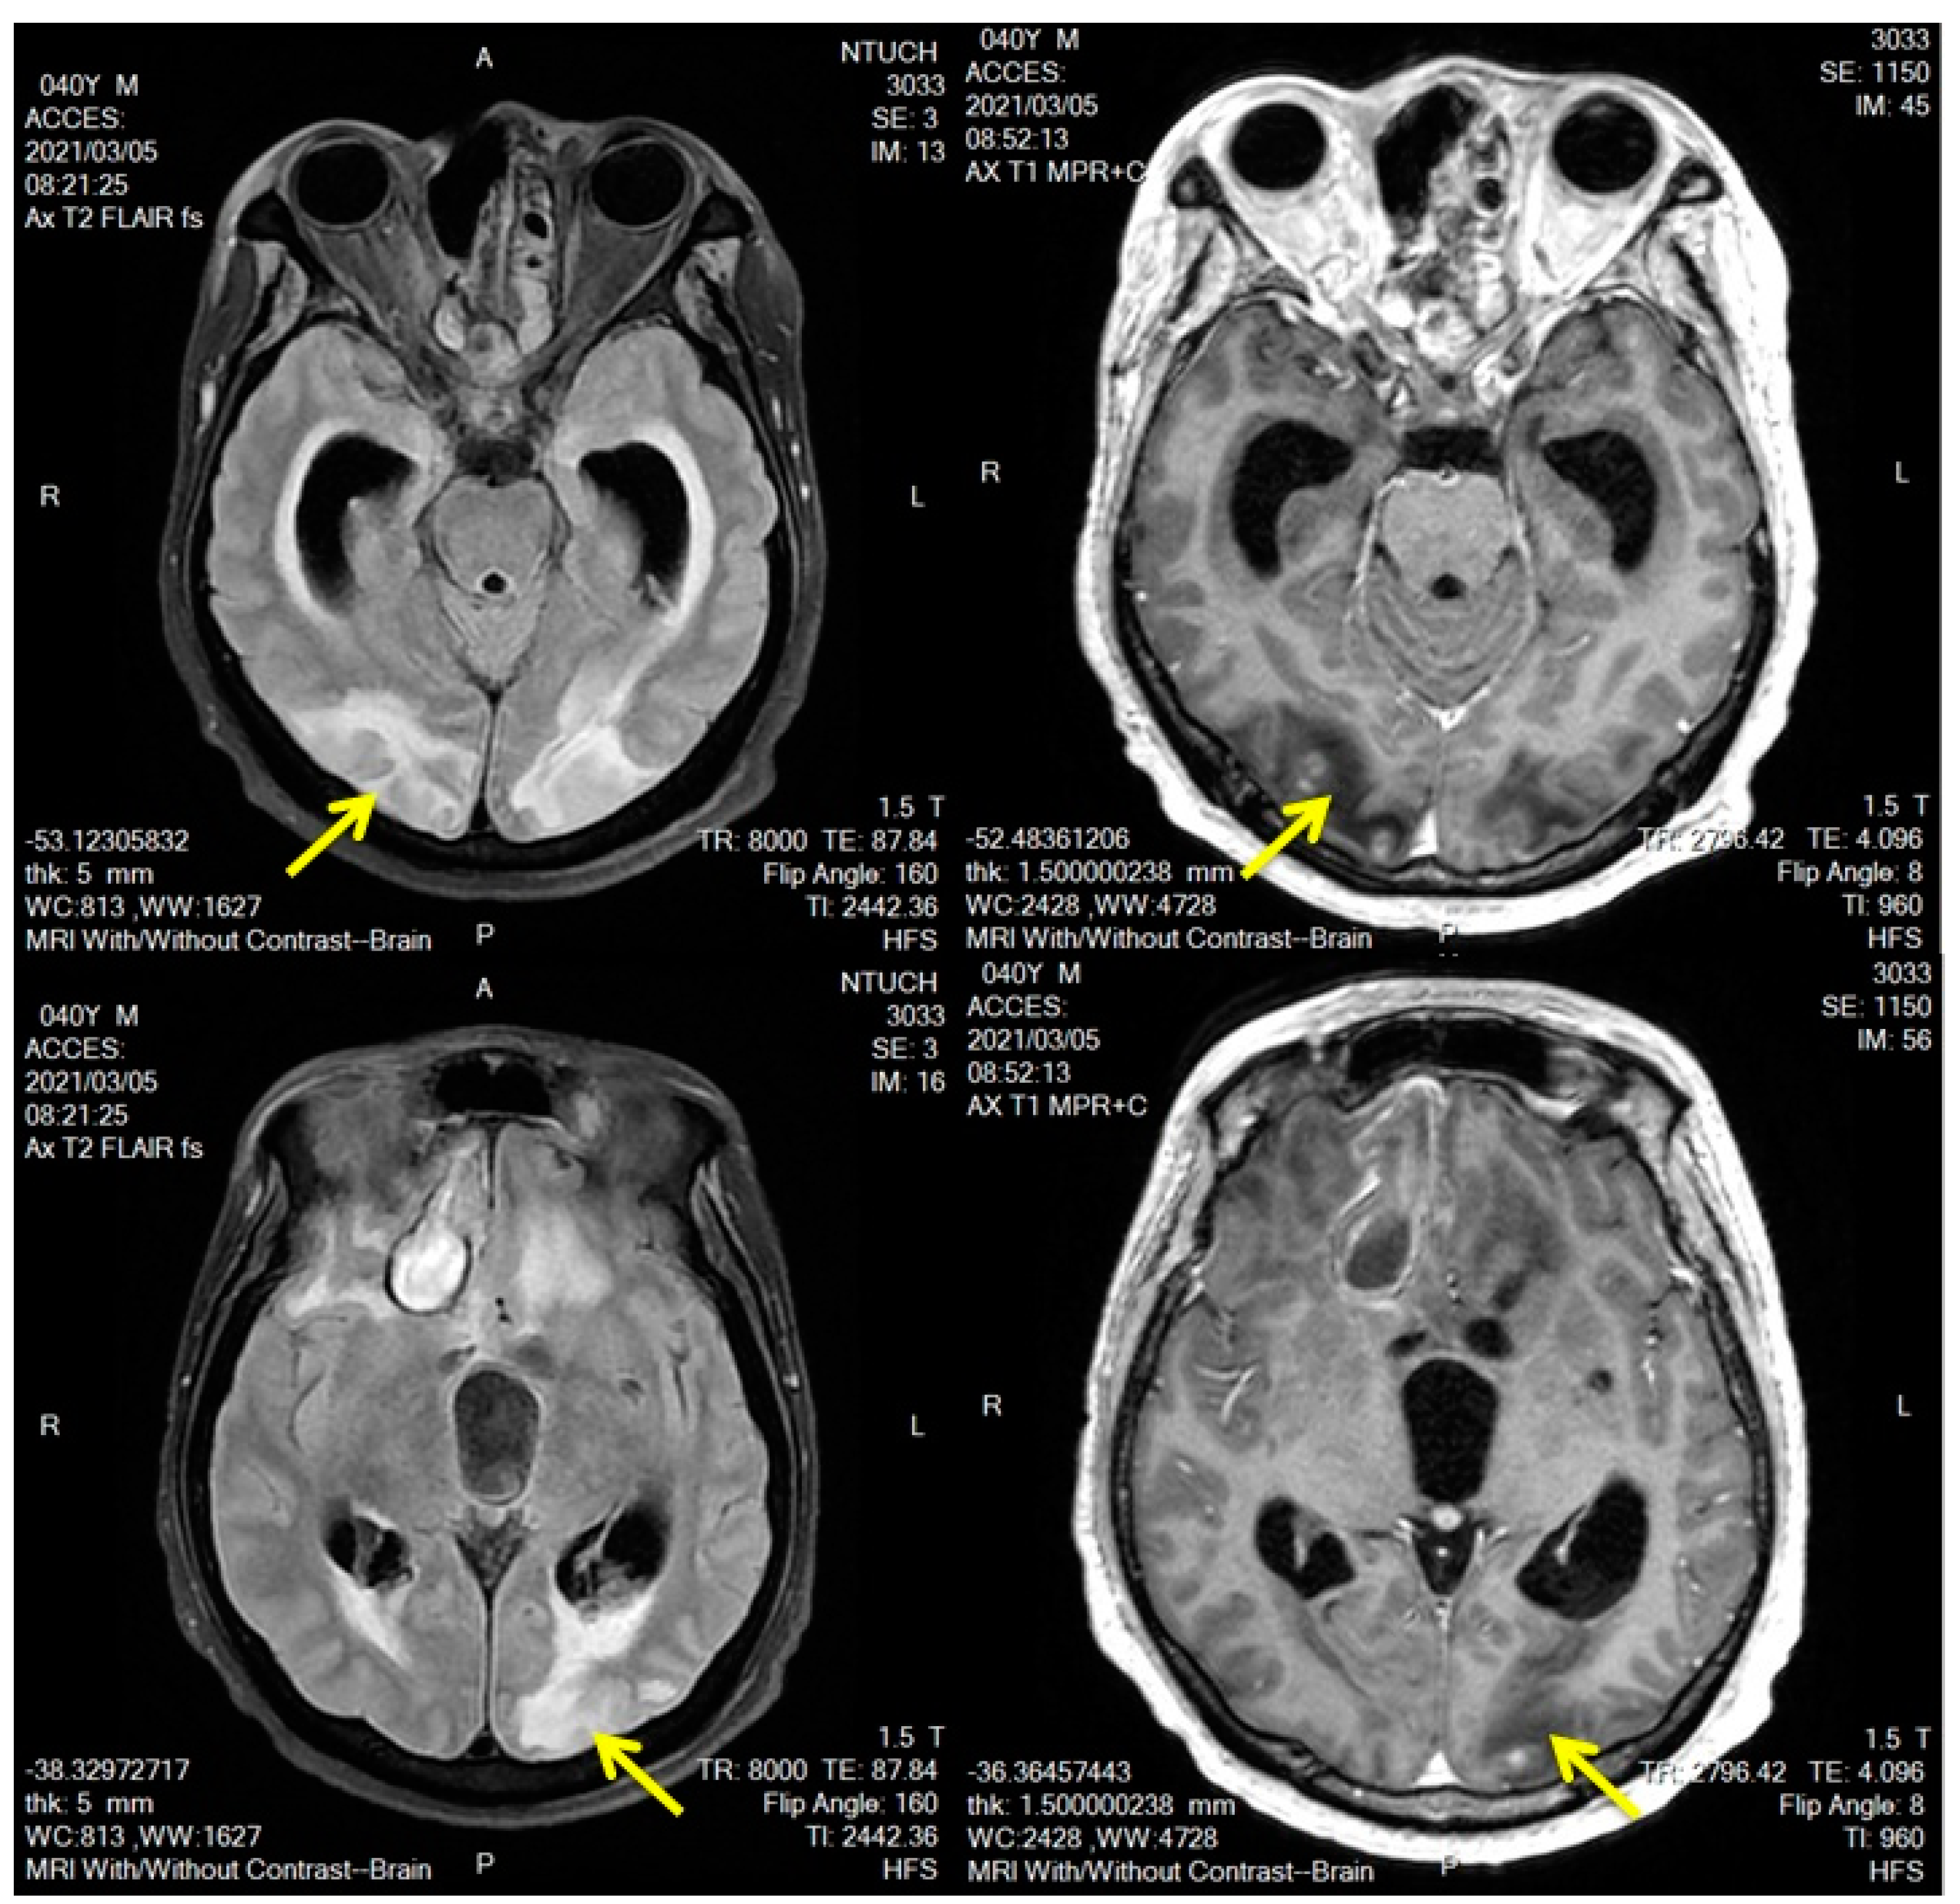

2. Case Description